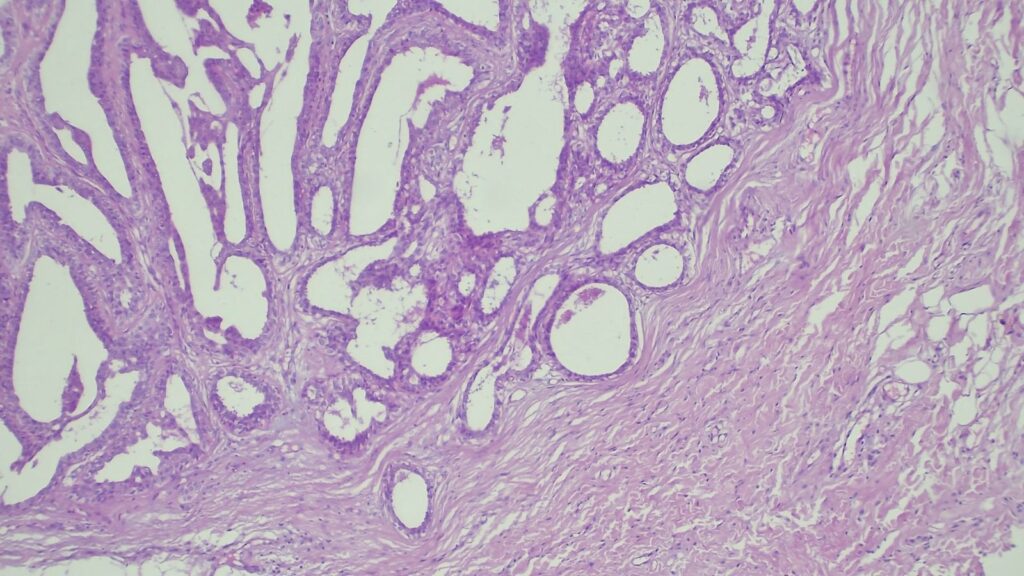

【病理形态学大解密:寻找良性证据】 仔细阅片后,专家指出了以下几个至关重要的形态学特征(见附带病理切片图):

✅ 腺体发育良好,呈圆形和分叶状结构。 ✅ 边缘虽略不规则,但整体呈推挤性(pushing)和局限性生长。 ✅ 无弥漫性浸润结构。 ✅ 无促结缔组织增生性间质反应(No desmoplastic stromal reaction,这是排除浸润癌的核心点)。 ✅ 细胞学形态温和(Bland cytology)。 ✅ 在慢性炎症和纤维化的背景下,仅见单个典型的核分裂象。 在病变外周,腺体表现出被瘢痕样间质压迫和塑形的特征,而不是破坏性或浸润性生长。